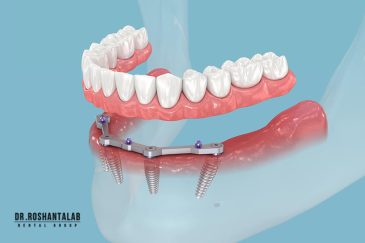

🔸کاشت ایمپلنت فلپ لس یا بدون جراحی و بدون بخیه زیر سه دقیقه

🔸 کاشت دندان یک روزه ( کشیدن و کاشت همزمان )

🔸 ایمپلنت دیجیتال و ساخت روکش دیجیتال